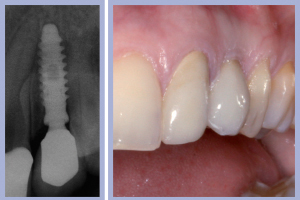

- Figg. 29a, b Manufatti di destra e radiografia di controllo. Si noti l’ottima integrazione tissutale

- Figg. 30a, b – Manufatti di sinistra e radiografia di controllo

La valutazione clinica al momento della consegna dei manufatti e clinico-radiologica a 3 mesi dalla consegna manifestava una completa integrazione tissutale con eccellente recupero estetico e funzionale (Figg. 29-30).

La consegna dei manufatti a supporto implantare veniva effettuata previa cementazione extra-orale degli stessi (Figg. 26-28).